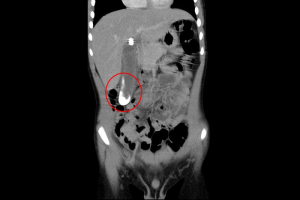

二零二二年八月中旬,六歲的陳小弟因腹痛不止而就醫,經超音波和電腦斷層檢查,發現膽囊裡竟有大片膽結石堵住與膽管的銜接處,造成發炎、引起疼痛,在花蓮慈濟醫院小兒部陳明群與張雲傑醫師的會診後,判斷陳小弟是罕見的「小兒膽結石」。